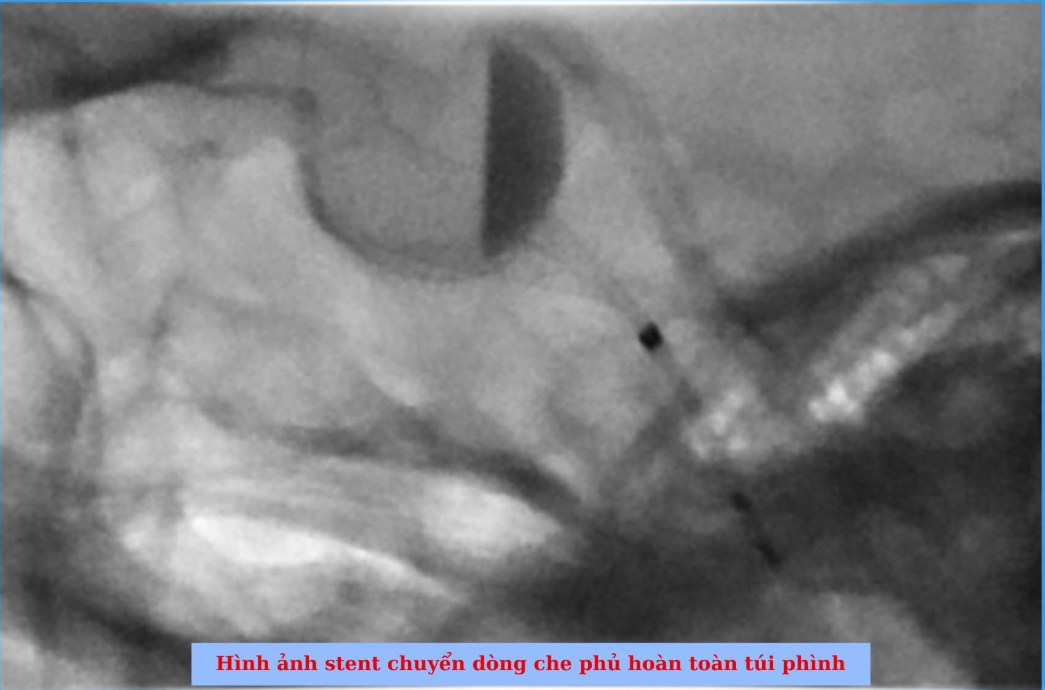

Ca can thiệp diễn ra trong vòng 1 giờ đồng hồ và kết thúc thành công. Túi phình đã được che phủ hoàn toàn bởi stent chuyển dòng. Đặc biệt, trong suốt quá trình can thiệp, bệnh nhân luôn giữ được trạng thái tỉnh táo và không xuất hiện bất kỳ biến chứng nào.

Stent chuyển dòng hoạt động dựa trên cơ chế điều hướng lại dòng máu trong lòng mạch. Khi được đặt vào đúng vị trí, stent sẽ thay đổi hướng dòng chảy của máu, giảm áp lực tác động lên túi phình. Nhờ đó, máu trong túi phình dần hình thành huyết khối và túi phình tự đóng lại theo thời gian.